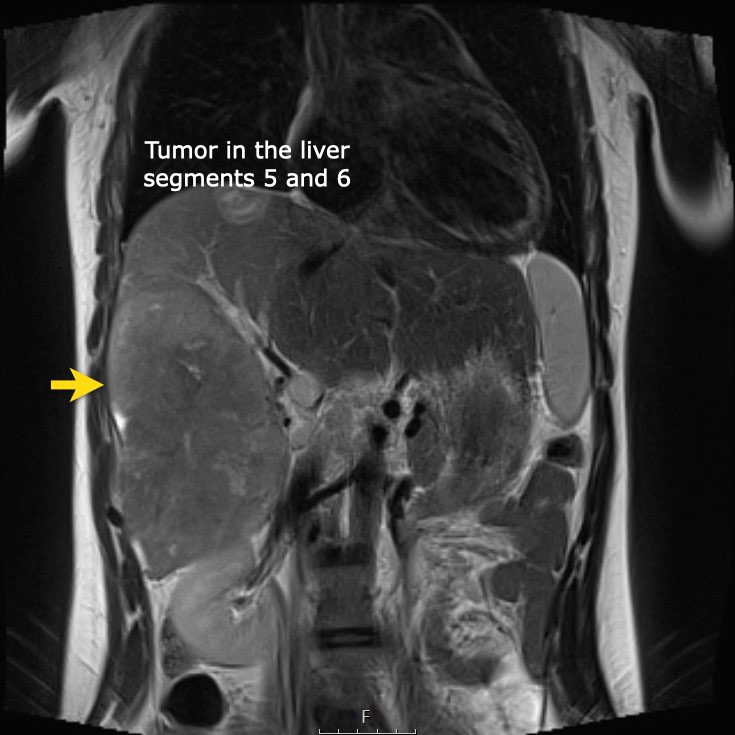

Ví dụ 1

Một bé gái 17 tuổi nhập viện với triệu chứng đau bụng vùng thượng vị. Siêu âm phát hiện một khối u gan lớn.

Trên MRI thấy khối u ở phân thùy gan 5 và 6 với các tổn thương vệ tinh ở phân thùy 7 và 8 (mũi tên). Có huyết khối u trong tĩnh mạch cửa phải (đầu mũi tên) và nhiều di căn phổi (*).